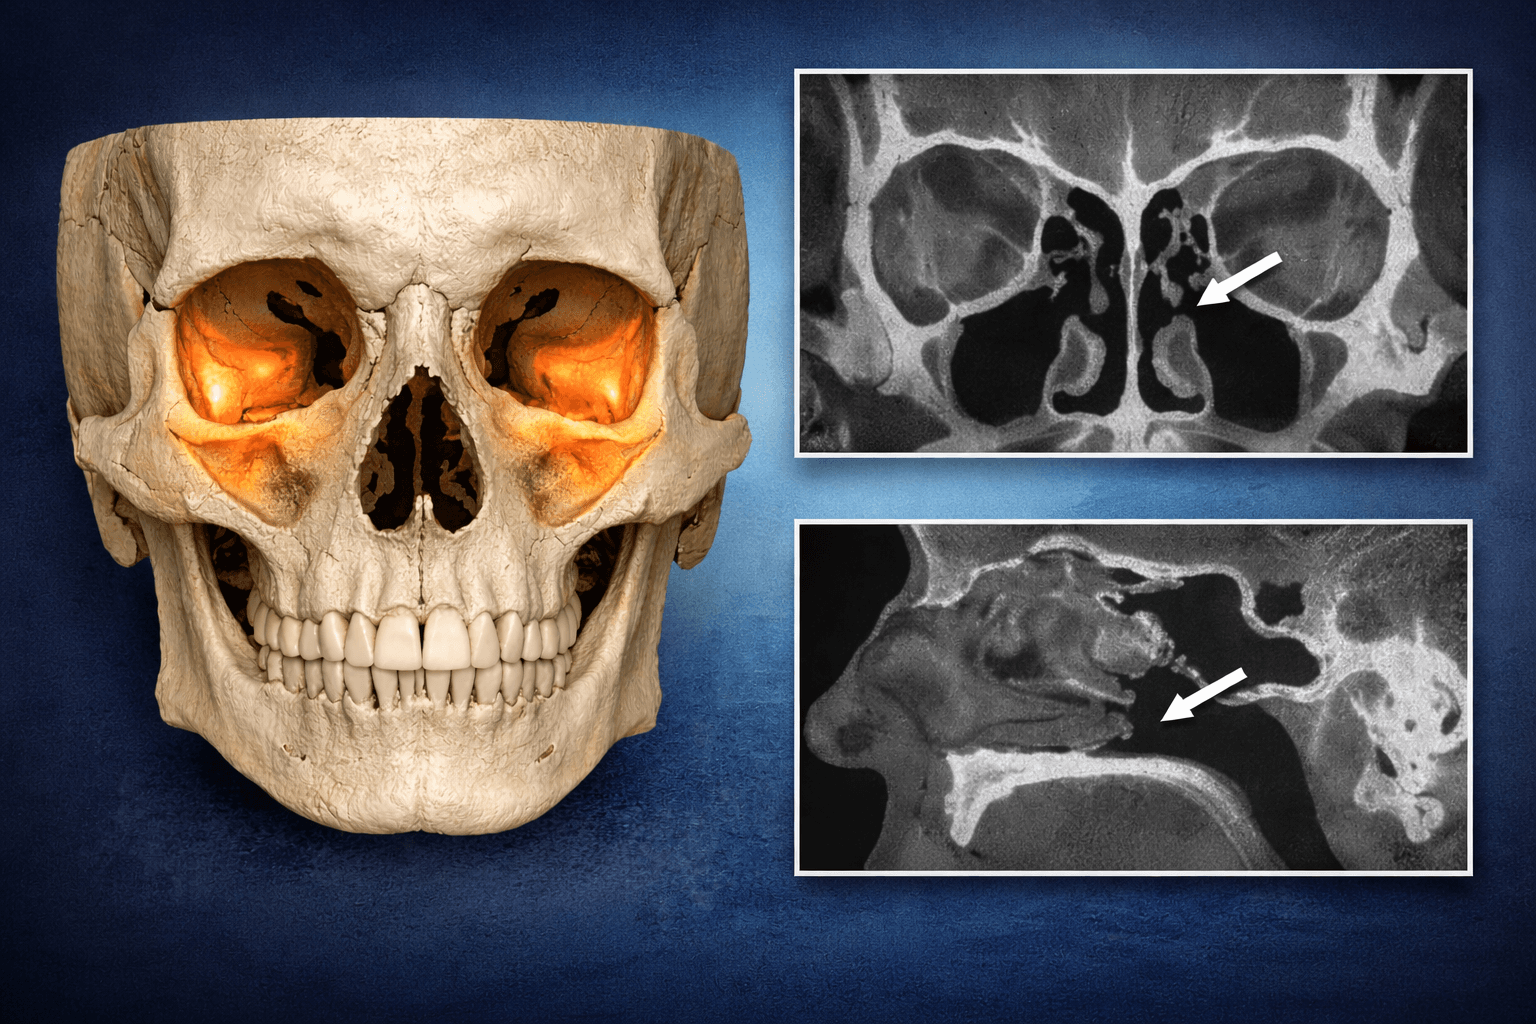

La clave es saber exactamente cuánta altura ósea hay y dónde está el seno maxilar. Por eso, en casos implantológicos avanzados, la planificación con CBCT (TAC dental) ayuda a decidir la técnica adecuada y reducir riesgos.

📋 Antes de realizar el procedimiento, el dentista realizará una evaluación exhaustiva del maxilar superior utilizando radiografías y/o tomografías computarizadas para determinar la cantidad y calidad del hueso disponible, así como la posición del seno maxilar.